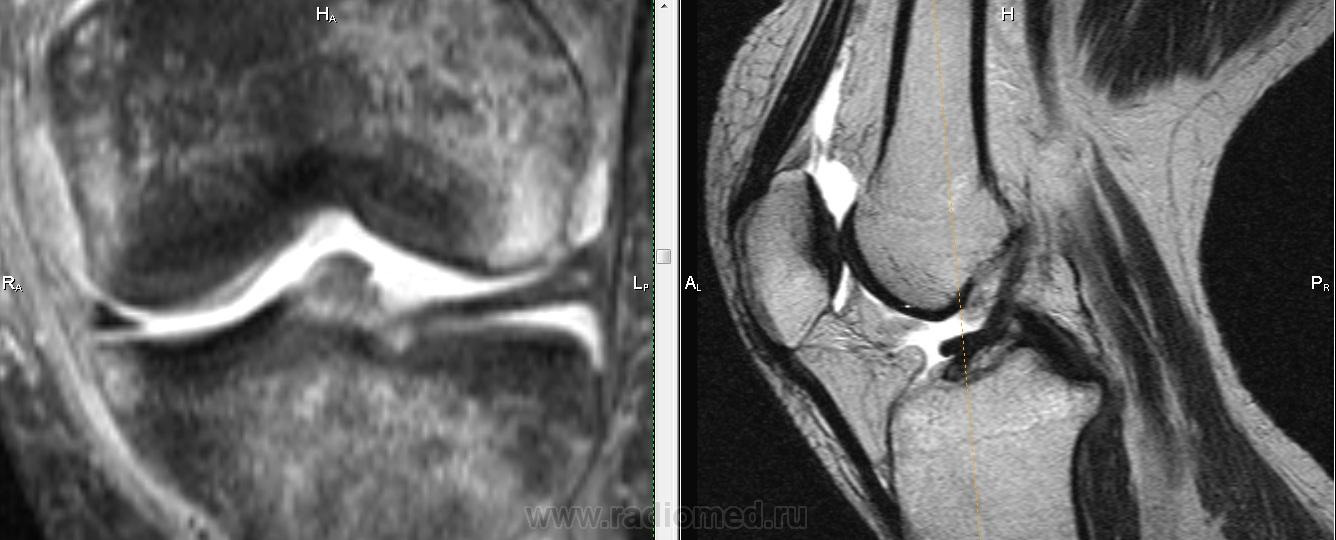

Падение с велосипеда. Вперед выступает фрагмент ПКС?

Не очень понятно, Михаил Александрович.Как-будто бы симптом "двойной  крестообразной связки", но не совсем похоже: при  этом  связка как-бы дугообразно идет.И мениски визуально вроде бы целы.Не может это быть фрагментом  переднего рога мениска?

Трудно сказать, на фрагмен мениска более похоже. Да и ПКС не отечная и внутренний мениск какой-то дефицитный. Если вопрос о цесостности ПКС обычно косая проекция выручает.

Думаю , тут фрагмент   переднего рога и части тела  латерального мениска ,  он(фрагмент) совсем  оторвался и уплыл кпереди .